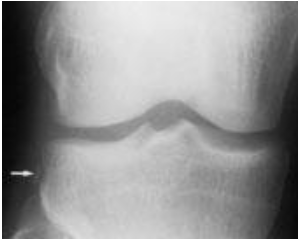

Fraktur Segond: Fraktur avulsi kecil pada plateau tibia lateral. Temuan ini dianggap patognomonik untuk robekan Anterior Cruciate Ligament (ACL) yang menyertainya dan merupakan indikasi kuat untuk MRI.

Gambar 2. Fraktur Segond (panah), avulsi kortikal pada proximal lateral tibial plateu yang juga melibatkan kapsul lateral

Kehadiran fraktur avulsi yang halus, seperti fraktur Segond, bukanlah temuan yang terisolasi; ini adalah hasil langsung dari gaya tarik (tensile) pada ligamen selama peristiwa cedera yang parah. Tulang pada titik insersi mengalami kegagalan sebelum ligamen itu sendiri. Oleh karena itu, melihat fraktur Segond pada foto Rontgen secara fungsional setara dengan melihat "jejak kaki" dari robekan ACL. Pemahaman ini mengubah radiografi dari alat pencitraan tulang menjadi alat skrining jaringan lunak yang kuat. Bagi seorang dokter umum, pengetahuan ini dapat mengubah praktik secara fundamental. Pasien dengan fraktur "chip" yang tampaknya "minor" (fraktur Segond) pada foto Rontgen mungkin akan dikelola secara konservatif. Namun, pemahaman bahwa tanda ini memiliki asosiasi hampir 100% dengan robekan ACL menuntut perubahan tatalaksana segera: non-beban tumpu, imobilisasi lutut, dan rujukan segera ke ortopedi untuk kemungkinan evaluasi MRI dan bedah. Hal ini mencegah kesalahan diagnosis cedera ligamen mayor sebagai "keseleo" atau fraktur minor, sehingga menghindari instabilitas sekunder dan degenerasi sendi jangka panjang.